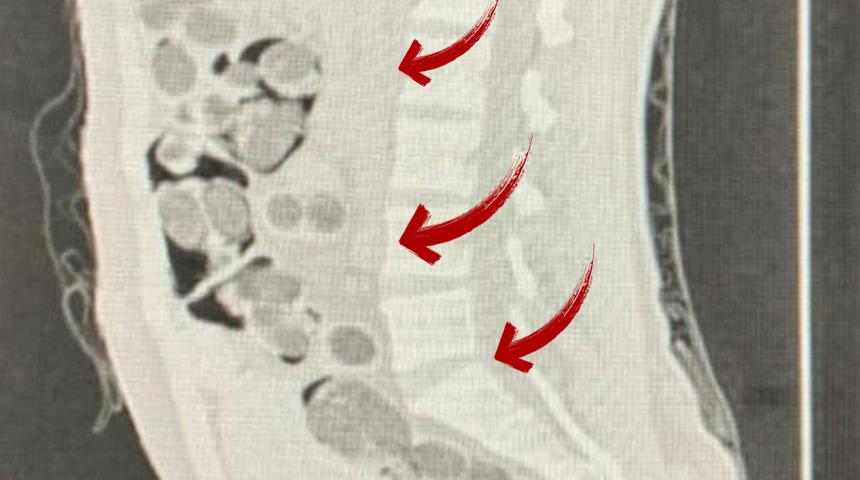

Şüpheli ile alıcı, gözaltına alındı. Denizli Devlet Hastanesi'ne götürülüp, röntgeni çekilen yabancı uyruklu şüphelinin midesinden 219 paket halinde 1 kilo 144 gram skunk, 178 gram metamfetamin, 90 uyuşturucu hap ve 7 gram Afyon sakızı çıktı. Paketteki uyuşturucular doğal yollarla çıkartılırken, 2 şüpheli işlemlerinin ardından tutuklandı.